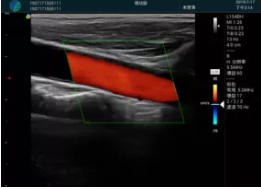

頸動(dòng)脈血流充盈飽滿(mǎn),無(wú)外溢

肝內(nèi)血管顯示清晰,血流敏感無(wú)外溢